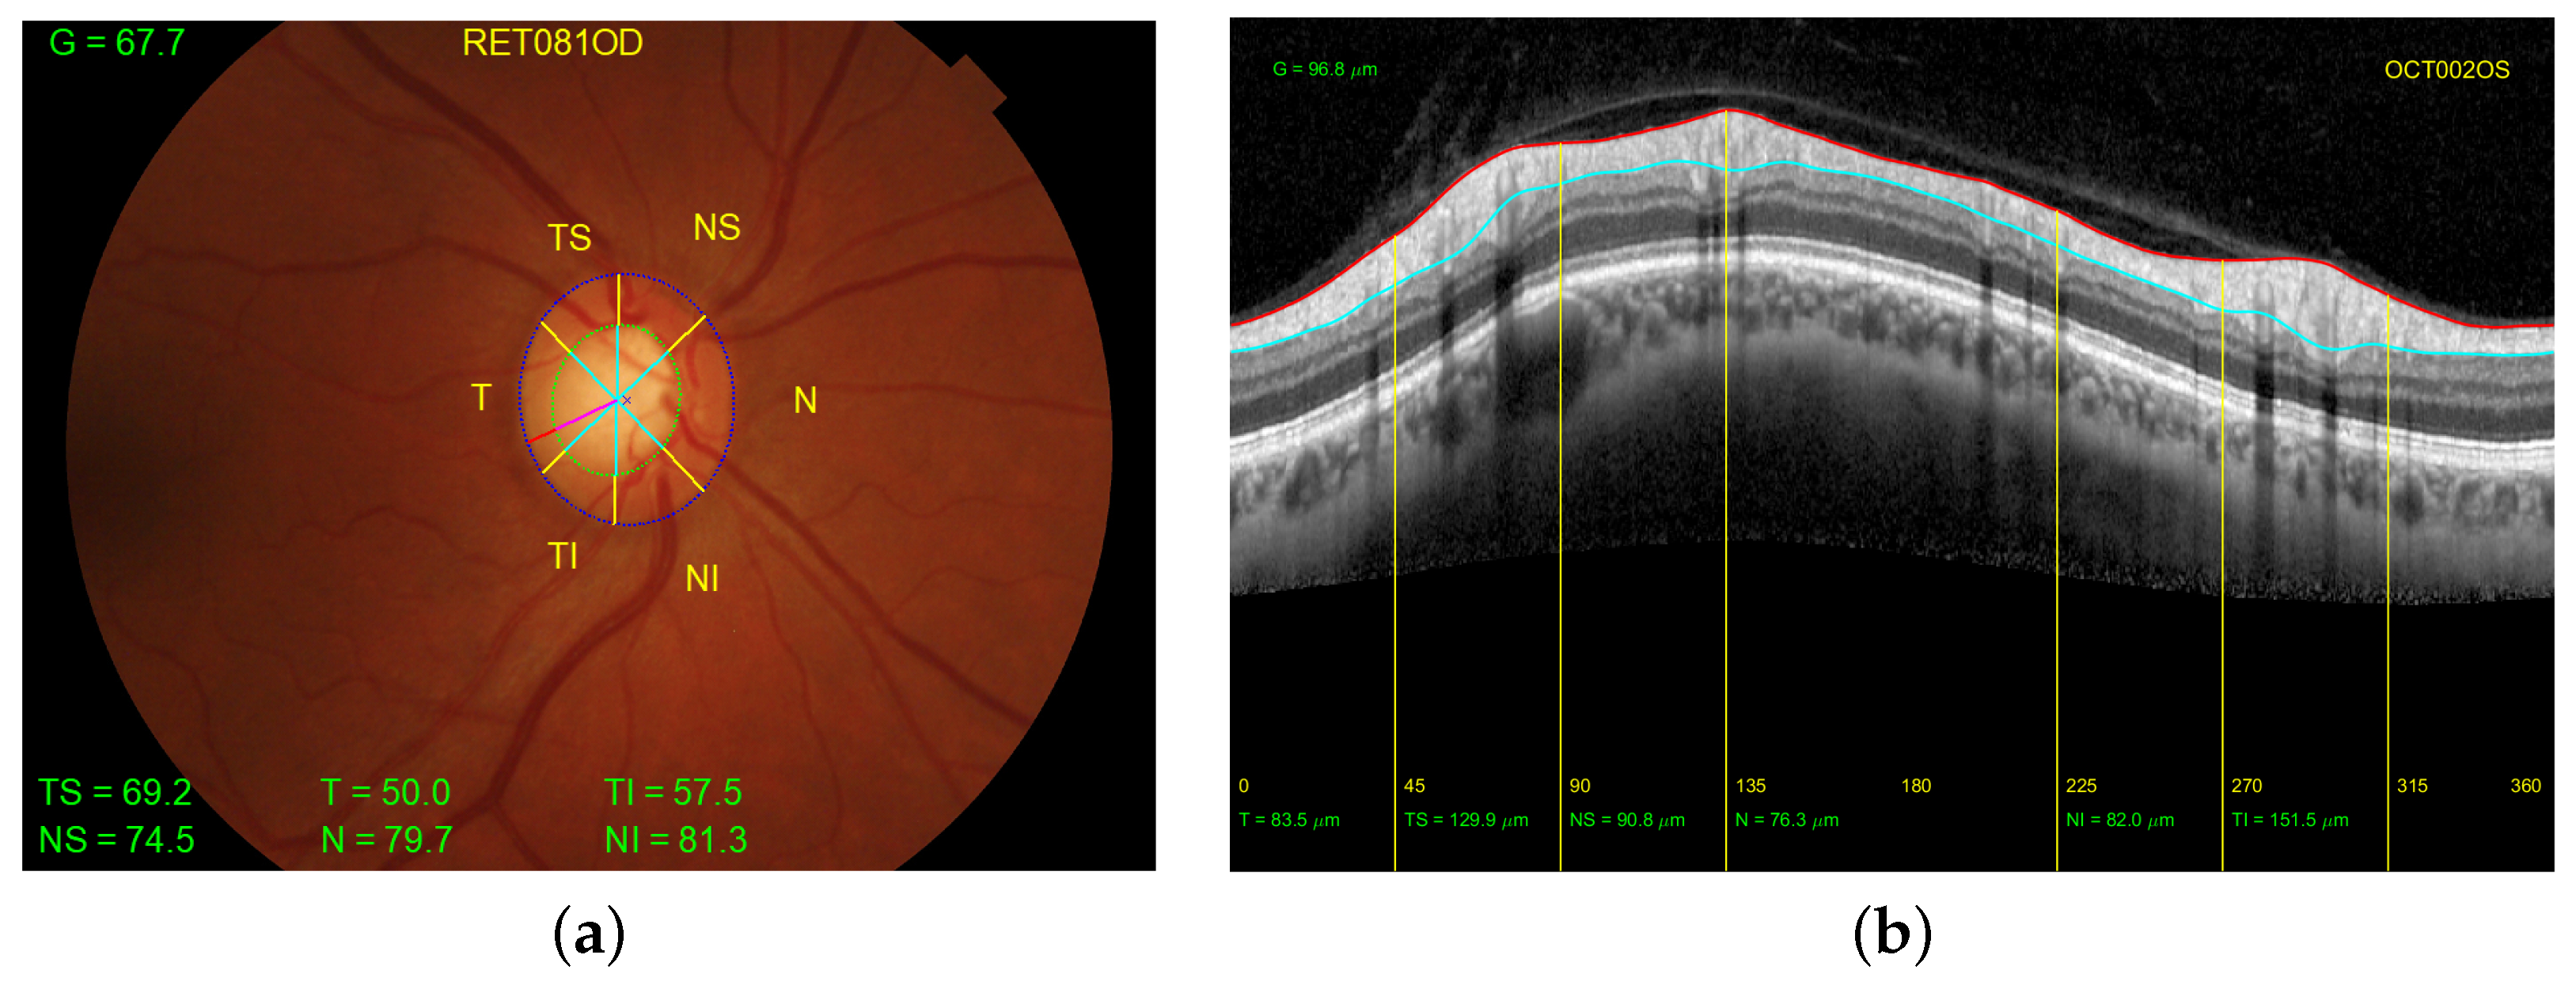

In order to facilitate the study and extraction of features from retinographies and OCTs, the structures provided by these two imaging modalities are typically divided into six sectors: temporal (T), temporal superior (TS), nasal superior (NS), nasal (N), nasal inferior (NI), and temporal inferior (TI). An additional sector (G) refers to the average of all sectors. Note that sectors T and N cover an angle of ninety degrees, while the other sectors cover an angle of forty-five degrees. Figure 1 depicts the distribution of the sectors for both the right and left eyes. Figure 2 shows the correspondence of the sectors in a retinal fundus image with an OCT.

Figure 2. Distribution of the sectors. (a) Retinography of the right eye of a patient with the width of the rim from the manual segmentations of the optic disc (in dotted blue line) and excavation (in dotted green line). (b) Peripapillary B-scan OCT with the measurement of the thickness of the retinal nerve fiber layer delineated between the red line (top) and the light blue line (bottom). In both figures the yellow lines indicate the borders of each sector of the eye.